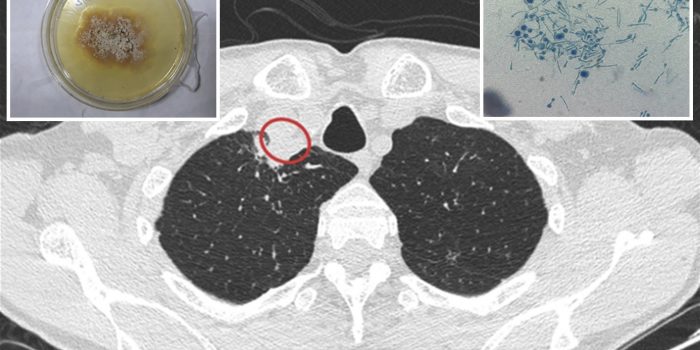

印度61岁的农民,他是一个植物真菌学家、感染引起的一种罕见真菌疾病Chondrostereum purpureum,导致“银叶”的真菌疾病的植物。这是首次记录的人类感染了真菌,这是致命的植物。

病人得到了两个疗程的抗真菌药物治疗两个月,和脓被送到了一个世卫组织合作中心在印度北部进行测试。研究人员指出,只有少数的数以百万计的真菌能感染人类和动物。

她进一步解释说,人在加尔各答的情况下可能被暴露在一个令人难以置信的大量的孢子,可能由于他的实验或植物的工作。Bignell教授强调,没有引起恐慌,但补充道:“这是一个新事物,我们也不知道。”